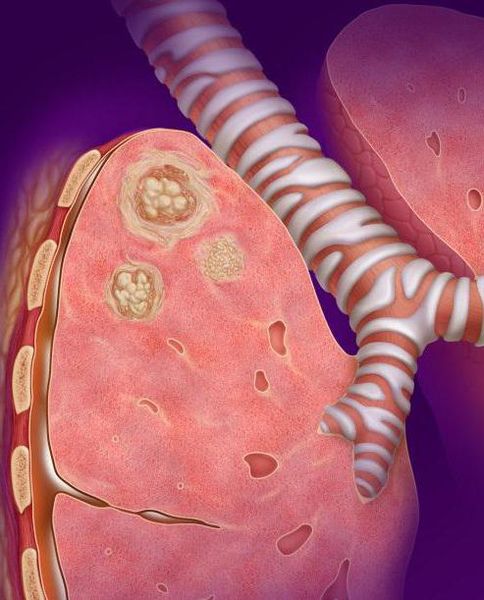

Казеозная пневмония (Caseous pneumonia) — это одна из самых тяжёлых форм туберкулёза лёгких, при которой развивается гнойно-некротическое воспаление, т. е. появляется большое количество специфического туберкулёзного гноя — казеоза, что приводит к массивному разрушению лёгкого. Такое воспаление является необратимым, т. е. полное восстановление лёгких невозможно.

Казеозная пневмония быстро прогрессирует: воспаление распространяется в течение 2–6 недель. При этом она может поразить как одну долю лёгкого, так и полностью орган с обеих сторон. В результате гнойного расплавления тканей в месте поражения формируется одна или множество полостей (каверн) [1][2][3]. Этот процесс сопровождается сильнейшей интоксикацией, одышкой, слабостью, кашлем и повышением температуры до 39–40 °C.

Кавернозный туберкулёз